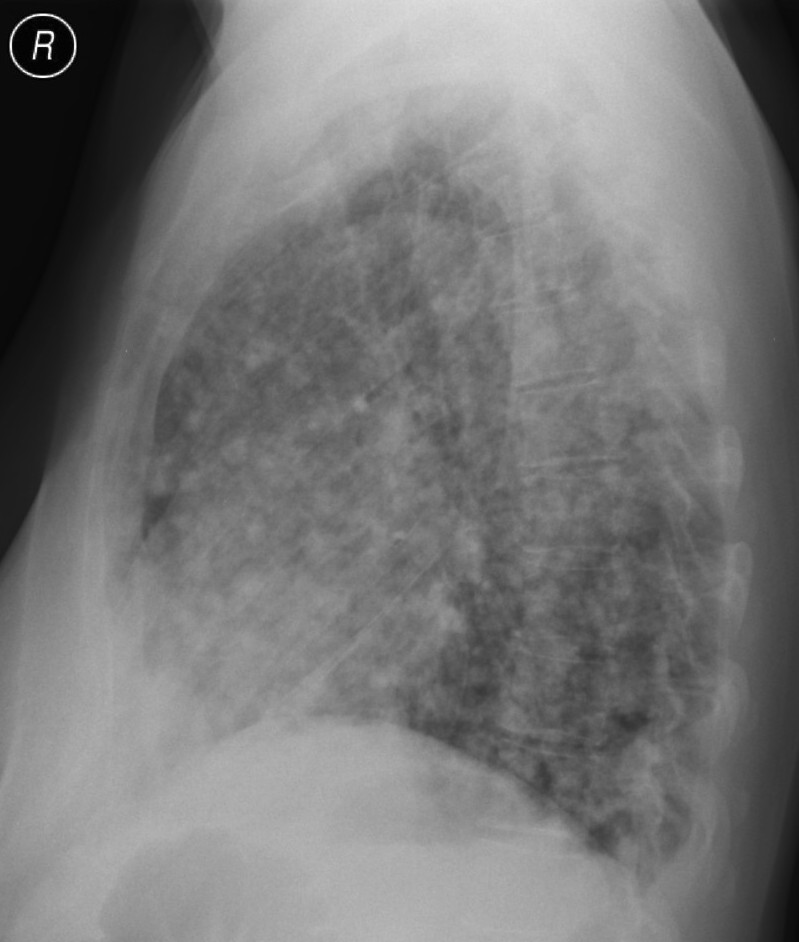

23. Pulmonary metastases, bidirectional (PA and right lateral) plain chest radiograph.

51 year old woman, endometrial carcinoma. Numerous ring shadows bilaterally in basal dominance (max. appr. 12 mm). Left pleural effusion of one finger wide.